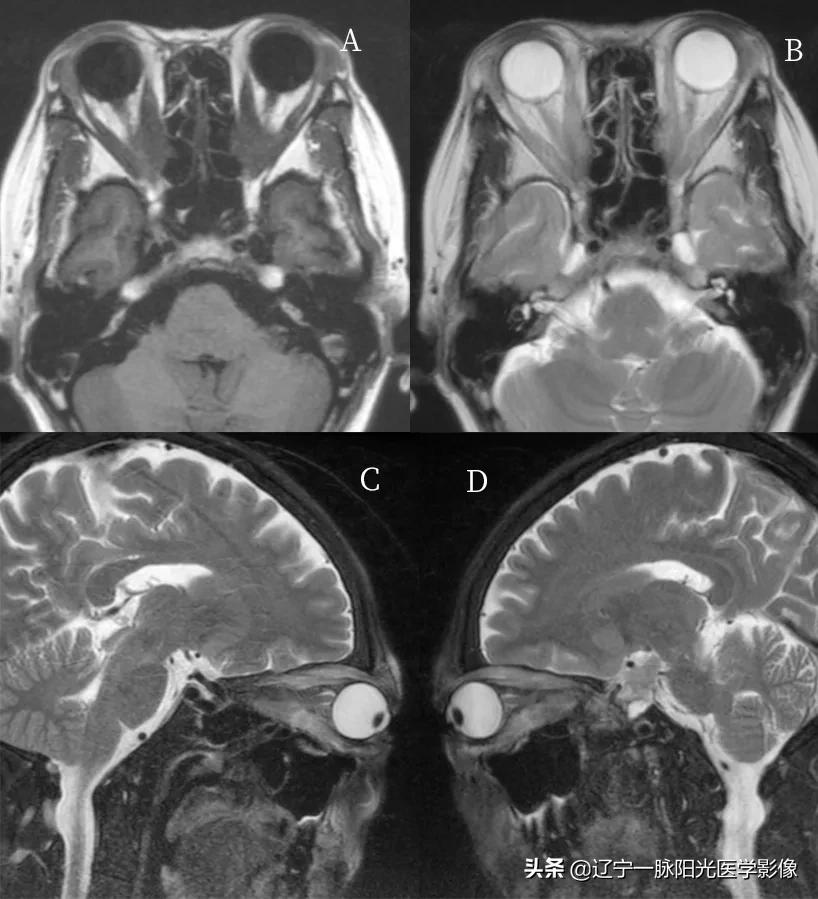

影像所见:

图 A、B、C、D 轴位、冠状位及矢状位示双侧眼球对称性突出,眼肌均匀增厚,以上、下直肌明显,球后脂肪减少

图 A、C、D 双侧球内玻璃体、晶状体密度正常。视神经走行正常,密度均匀,边界清楚

甲状腺眶病又称为 Graves 眶病,甲状腺功能异常伴有眼征者为 Graves 眶病

男女均可发病,中年女性居多,是眼球突出的最常见原因之一,一般双侧,也可单侧发病,病理改变为淋巴细胞和浆细胞的浸润,并有散在的肥大

影像学一般依靠 CT、MRI 检查,诊断依据为眼外肌肌腹增粗而附着于眼球壁的肌腱不增粗,而且常是双侧下直肌、上直肌、内直肌肌腹增粗